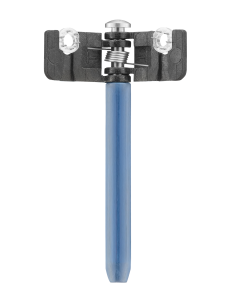

Πλαστική – Γναθοπροσωπική Χειρουργική

Λεπτομέρεια, λειτουργικότητα, αισθητική αρτιότητα

Με εξειδίκευση στις πλαστικές και γναθοπροσωπικές επεμβάσεις, παρέχουμε προηγμένα ιατρικά υλικά και τεχνολογικές λύσεις που ανταποκρίνονται στις υψηλές απαιτήσεις της επανορθωτικής χειρουργικής. Η πολυετής μας εμπειρία εγγυάται ποιότητα, ακρίβεια και αξιοπιστία σε κάθε στάδιο της χειρουργικής διαδικασίας.

Η εταιρεία μας, σε συνεργασία με κορυφαίους διεθνείς κατασκευαστές, διαθέτει στην ελληνική και κυπριακή αγορά εξειδικευμένα υλικά και εργαλεία, που ξεχωρίζουν για την ακρίβεια, τη βιοσυμβατότητα και το άρτιο αισθητικό τους αποτέλεσμα.

Στην κατηγορία Πλαστικη- Γναθοπροσωπική Χειρουργική, θα βρείτε επιλεγμένα προϊόντα υψηλής ποιότητας, σχεδιασμένα για:

• Μείωση του χρόνου επέμβασης

• Επιτάχυνση της διαδικασίας αναστόμωσης

• Ταχύτερη επούλωση, Λιγότερη Τάση, Βελτιωμένη Αισθητική

Δείτε αναλυτικά τα προϊόντα μας και ανακαλύψτε την ποιότητα που μας καθιστά αξιόπιστο συνεργάτη σε δημόσια νοσοκομεία και ιδιωτικές κλινικές